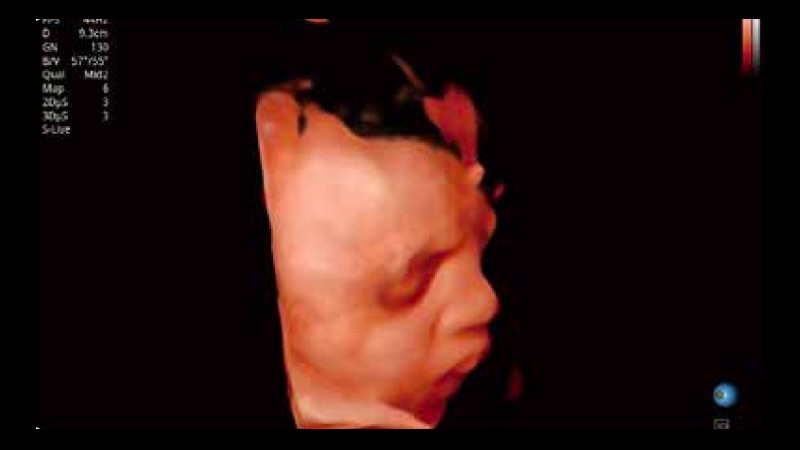

開立醫(yī)療通過不斷的技術(shù)創(chuàng)新,為大眾的生命健康提供持續(xù)關(guān)愛。P12 Plus采用全新一代超聲成像平臺,新平臺旨在將真實還原組織解剖結(jié)構(gòu)作為首要目標(biāo)。平臺采用全新集成化硬件模塊,搭載新一代芯片,系統(tǒng)性能得到大幅提升,為您的診斷提供了豐富的臨床信息。優(yōu)異的圖像表現(xiàn),豐富的探頭配置,全面的應(yīng)用功能,為您日常診斷提供了可靠的助手。

P12 Plus

彩色多普勒超聲診斷系統(tǒng)